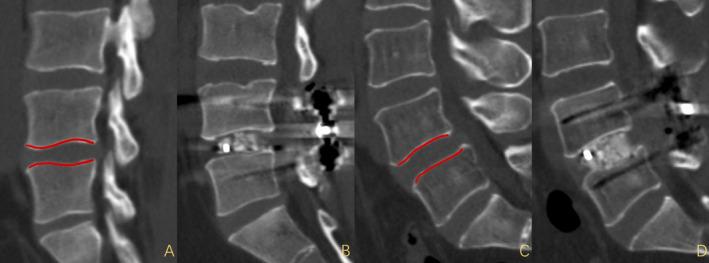

Pear-shaped disc could increase the risk of intraoperative end-plate injury, which may lead to postoperative sclerotic Modic Changes (MCs). However, there are no studies on the relationship between pear-shaped disc and postoperative sclerotic MCs. Therefore, this study investigates the risk factors for postoperative sclerotic MCs following transforaminal lumbar interbody fusion (TLIF). Specifically, the study focuses on the impact of pear-shaped disc on the occurrence of postoperative sclerotic MCs and evaluates its influence on clinical outcomes.

A total of 411 patients undergoing TLIF between January 2018 and January 2022 were included. Among them, 50 developed postoperative sclerotic MCs, while 361 did not. The two groups were matched based on various parameters. Clinical and radiographic evaluations, including visual analogue scale (VAS), Oswestry disability index (ODI), lumbar X-ray, CT, and MRI, were performed. Statistical analysis included independent sample t test, Pearson's chi-square test, and binary logistic regression analysis.

After pairing, a total of 100 patients were included, including 50 patients in postoperative sclerotic MCs group and 50 patients in non-MCs group. There were 27 pear-shaped discs in the postoperative sclerotic MCs group, significantly higher than 7 in the non-MCs group (p < 0.001). Besides, BMI, endplate injury, and cage subsidence in the postoperative sclerotic MCs group were significantly higher than those in the non-MCs group, but the fusion rate was significantly lower than that in the non-MCs group. The postoperative and follow-up SL and surgical corrections of SL in postoperative sclerotic MCs group were significantly higher than those in non-MCs group. The independent risk factors identified for postoperative sclerotic MCs include pear-shaped disc and higher BMI.